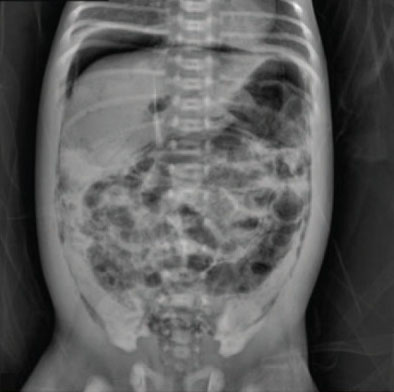

Diagnostics

NEC is clinically diagnosed from the symptoms presented by the infant—abdominal distention, bilious vomiting, and rectal bleeding with bloody stool—along with an x-ray of the abdomen showing pneumatosis intestinalis, intramural gas in the intestines (Figure 25.17). The only definitive diagnosis is made with a surgical sample or a postmortem assessment with tissue that shows histologic findings of intestinal inflammation, infarction, and necrosis.